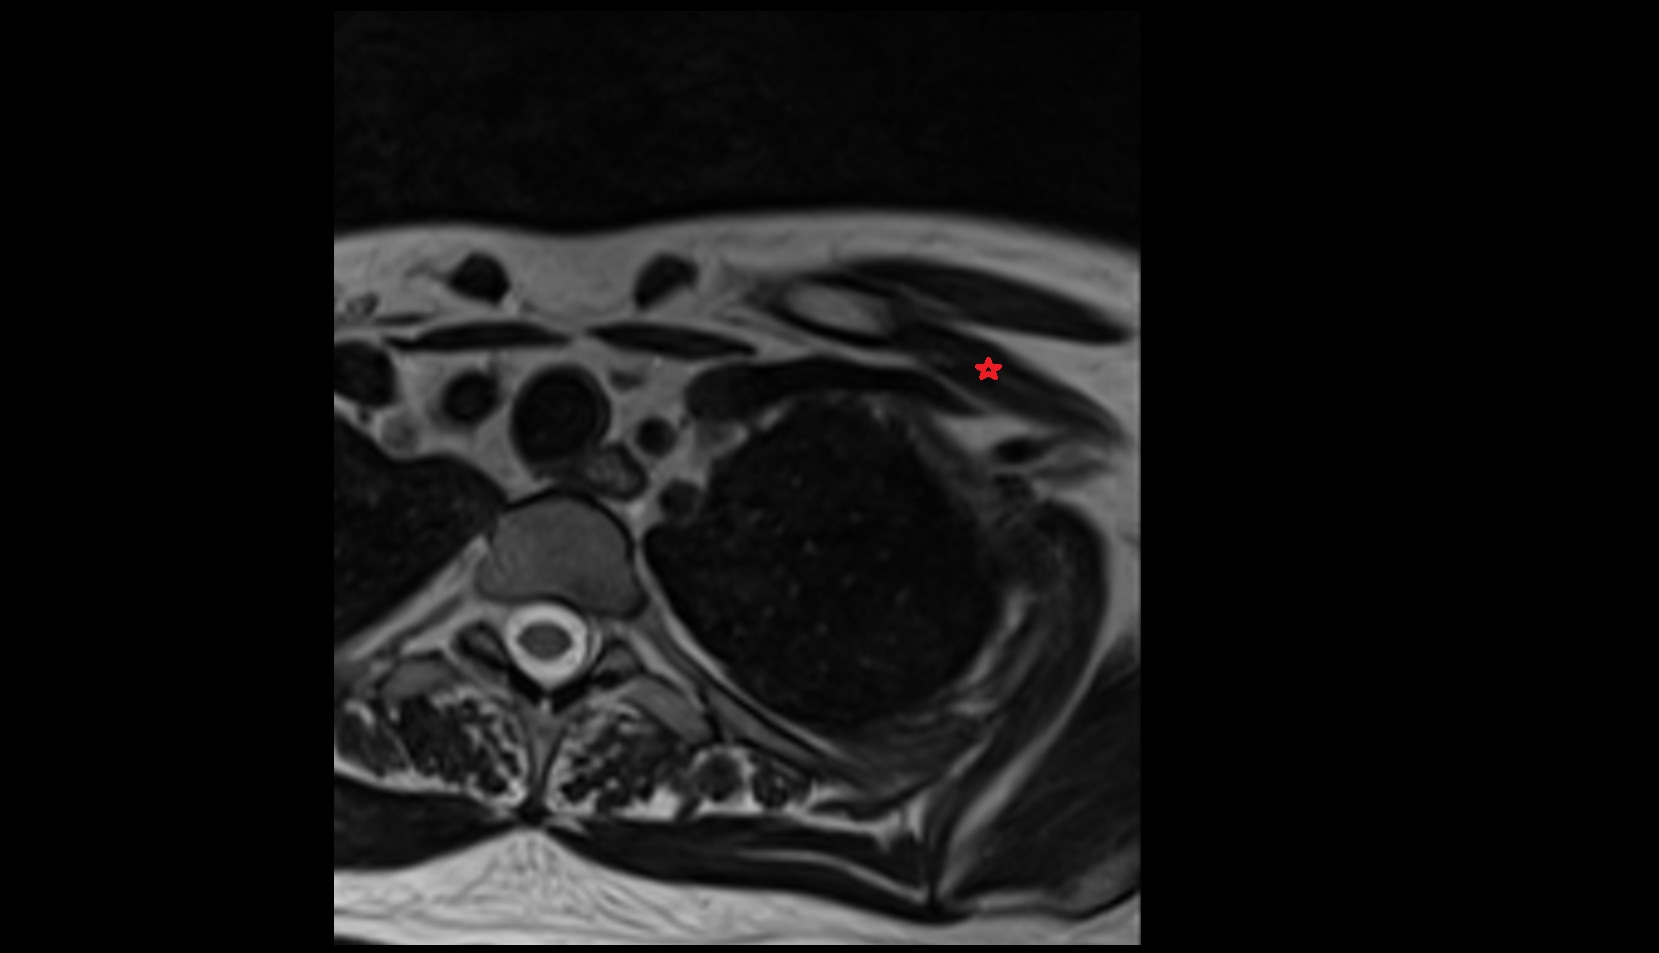

- Glenoid fossa

- Humerus

- Head of humerus

- Shoulder joint (glenohumeral joint)

- Adipose tissue (Shoulder)

- Supraspinatus tendon

- Infraspinatus tendon

- Subscapularis tendon

- Lesser tubercle of humerus

- Deltoid muscle